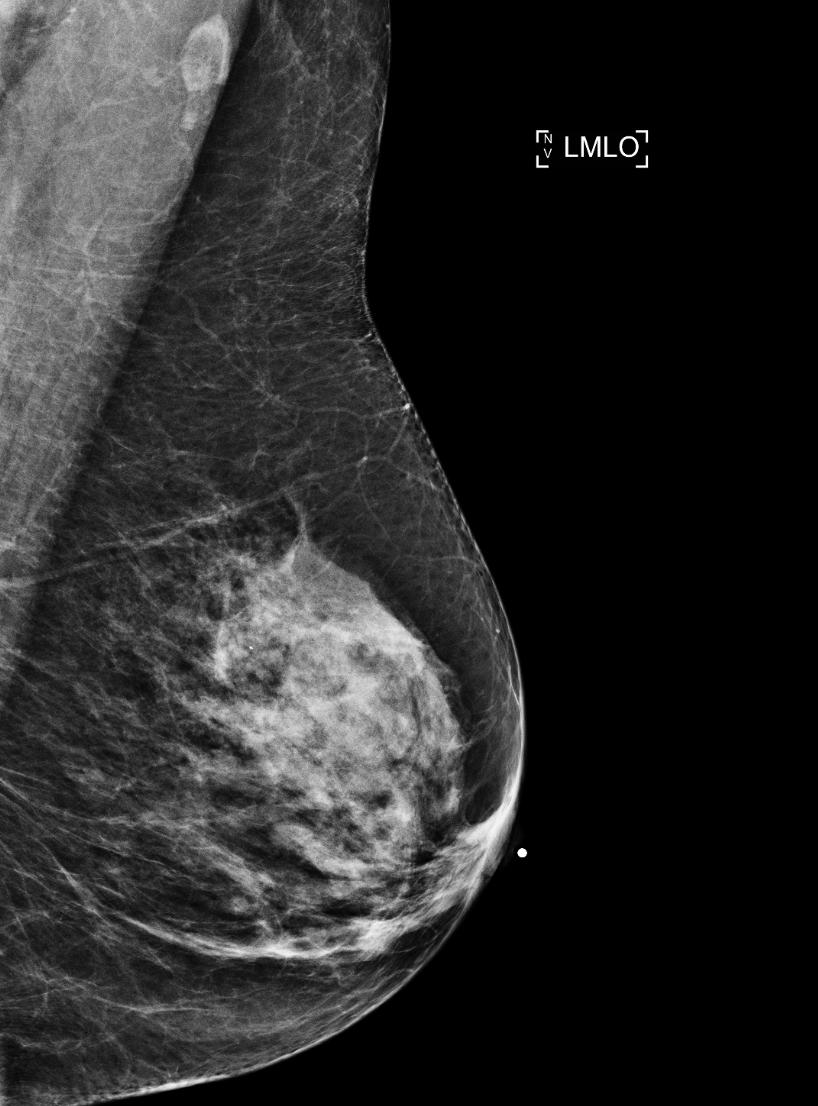

@kjgeras and@NanWu__, researchers at@nyuschoolofmed and@NYUDataScience, have created an AI diagnostic tool that's helping doctors detect breast cancer with more accuracy. Learn more about this important work on the new episode of "NYU Brainiacs": http://spr.ly/60151esTz pic.twitter.com/pGyfMRK20BHvala. Twitter će to iskoristiti za poboljšanje vaše vremenske crte. PoništiPoništi -

Researchers at the NYU Center for Data Science and the NYU School of Medicine have created an AI diagnostic tool that's helping doctors detect breast cancer with more accuracy. Follow this link to check out more: https://www.youtube.com/watch?time_continue=1&v=urJ7QEdhP_U&feature=emb_logo …pic.twitter.com/aHvfHEU8sE